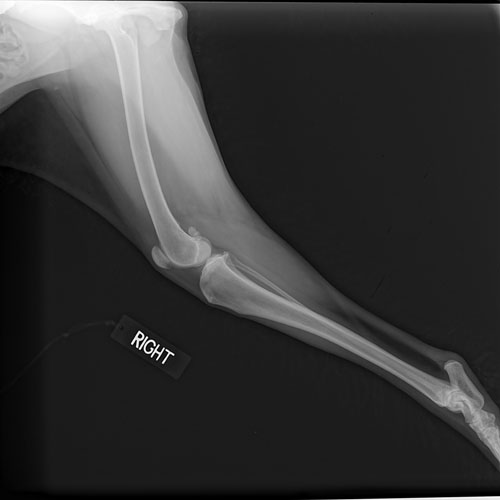

A painless, non-invasive procedure, digital radiography captures images of the body’s internal organs and skeletal system using very low doses of radiation. These images can be manipulated, enhanced, and contrasted, allowing our veterinarians to diagnose a condition more accurately. Typically, digital radiography can help with diagnosing fractures, locating foreign objects, detecting masses such as tumors, diagnosing pneumonia, discovering pregnancies, bladder stones, chronic arthritis, and certain spinal cord diseases.